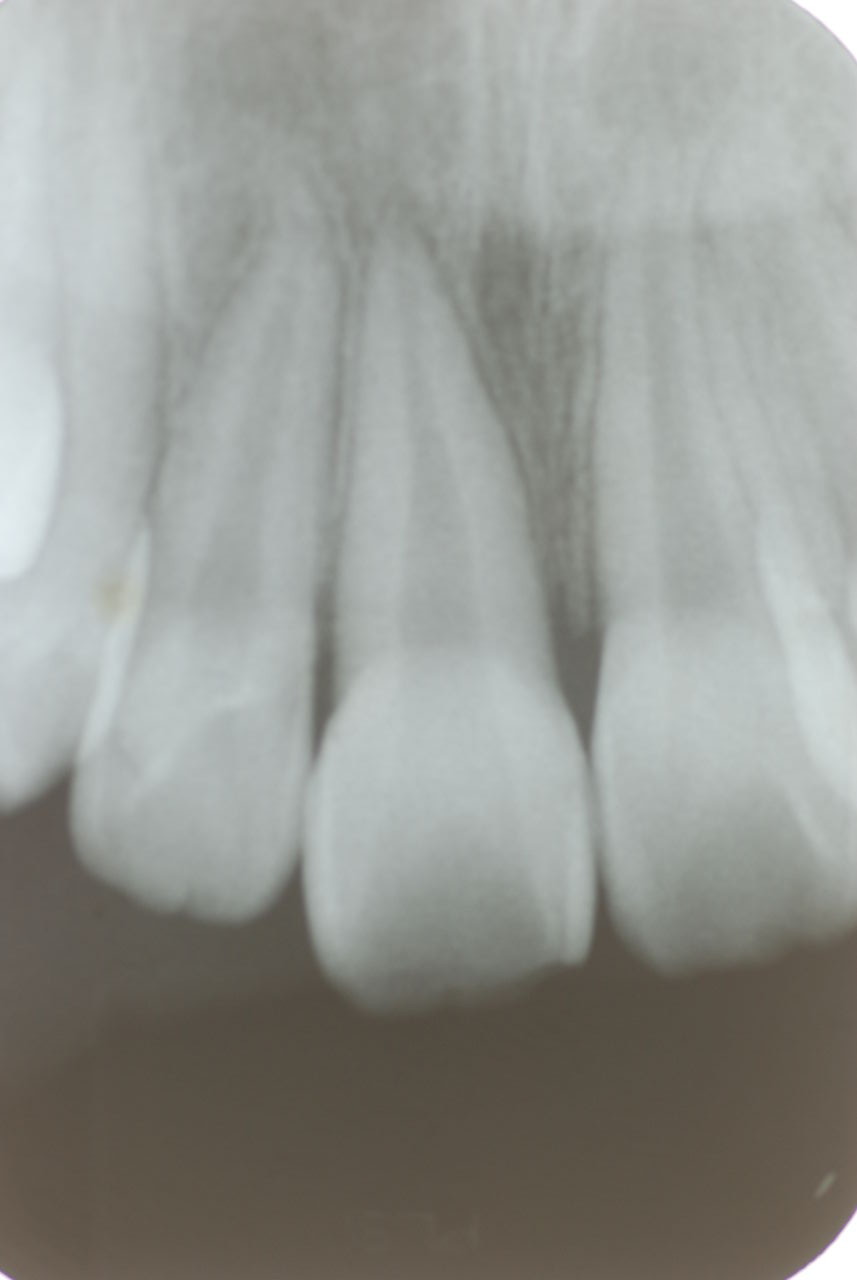

歯周病になっていましたが、少し色が黄色くなっているだけで比較的綺麗な歯の状態です。

平成9年来院神経を取り、同時に歯周病の話をしてそのまま来なくなっていたかたですが、たまたま一部欠けてきました。それで来院。

平成9年![40af2ca7-s[1]](https://livedoor.blogimg.jp/netdental/imgs/0/d/0d02b3dc.jpg)